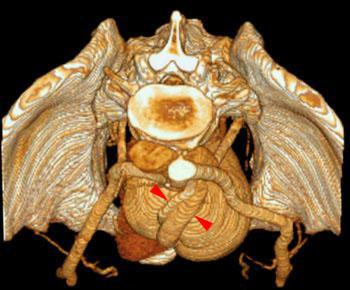

Riñón único pélvico